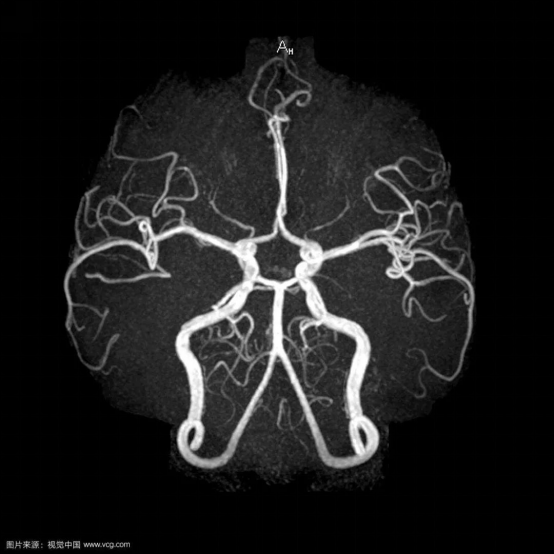

☆ 磁共振血管成像(MRA)的特点是无创、不需要注射造影剂就可以完成,可以在开展核磁共振检查时同时进行,但对脑血管疾病检查分辨率较差,可以作为脑血管疾病的筛查。

☆ CT血管成像(CTA)需注射含碘造影剂,在做之前需要了解肾功能情况(造影剂通过肾脏排泄),可以快速完成,病人痛苦少,分辨率较MRA有所提高,可以作为快速诊断脑血管疾病的方法及脑血管疾病的筛查。

☆ 全脑血管造影是最准确的脑血管造影方法,分辨率是最高的,是诊断脑血管疾病的“金标准”。在临床中,如果通过磁共振血管造影或CT血管造影检查,考虑有脑血管疾病的情况,特别是需要进一步治疗的时候,往往还是需要通过脑血管造影检查最后明确诊断,有些血管疾病在行脑血管造影检查的同时还可行介入治疗。